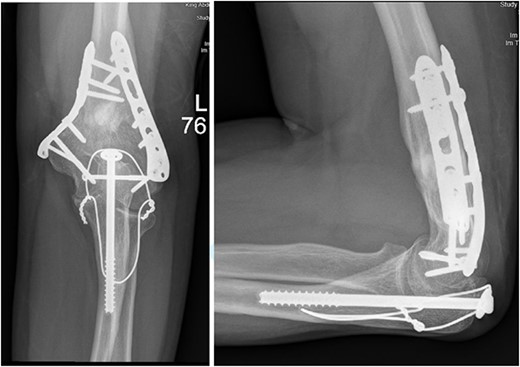

After surgery, the patient was taken back to the ICU and was followed daily by the upper limb orthopedic surgery team for wound care and change of dressings. Four days later, the patient’s condition had improved and he was assessed for distal neurovascular function, which was intact. Afterwards, range of motion was assessed, and no complications were reported before discharge. The patient was kept as an inpatient for almost two more months under the orthopedic trauma team for continuation of management and patient optimization. After discharge, the patient was followed in the orthopedics upper limb and trauma clinic for almost 3 years (Figs 4– 6).

(A). Late follow-up anteroposterior (AP) view of the left elbow after ORIF. (B) Late follow-up lateral view of the left elbow after ORIF.

(A) Late follow-up anteroposterior (AP) view of the left shoulder after ORIF. (B) Late follow-up lateral scapula (Y- view) view of the left shoulder after ORIF.

(A) Late follow-up internal oblique view of the left elbow after ORIF. (B) Late follow-up external oblique view of the left elbow after ORIF.

Our patient was followed afterwards for three years with serial x-rays. No signs of growth arrest or deformity due to our surgical intervention were noted. Instead, on follow up, our patient had a functional range of motion. Elbow range of motion was documented to be 30° extension to almost full flexion and intact pronation and supination. The range of shoulder motion was documented as full. Good healing was observed, but there was some hardware prominence that slightly affected the range of motion, and the patient will be booked for hardware removal. The patient was happy and satisfied about the overall outcome and restored functionality.